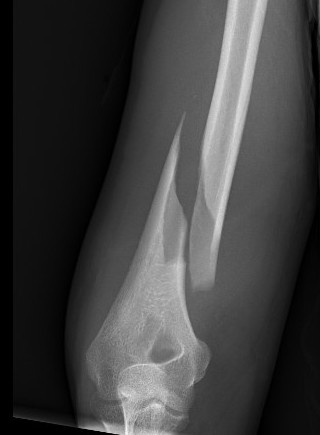

Holstein Lewis fracture

Holstein Lewis fractureHolstein Lewis

Holstein-Lewis JBJS Am 1963

- series of 7 oblique distal third fractures with radial nerve injury

- all were treated operatively

- nerve in fracture gap in 2 / impaled in 1 / severed in 2 / contused +/- in callus in 2

- advised against attempted closed reduction

- risk of contusing nerve between fragments

- advised early open reduction through anterolateral approach

- the radial nerve is closely assoicated with the fracture site and the fracture spike